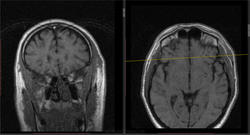

- https://radiomed.ru/sites/default/files/styles/case_slider_image/public/user/16807/5_9.jpg?itok=VBsarq3_

- https://radiomed.ru/sites/default/files/styles/case_slider_image/public/user/16807/6_6.jpg?itok=kUd4dXBb